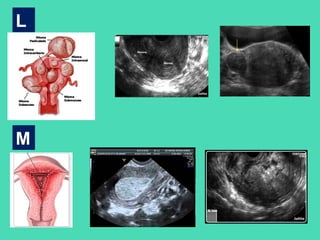

L

M

• PALM representa las alteraciones estructurales del útero.

COEIN representa las alteraciones no estructurales.

Basados en la terminología y patología propuesta, esta

clasificación muestra una primera parte descriptiva y otra

etiológica. Por ej., AUB-P corresponde a Hemorragia uterina

anormal-Pólipo.

Adicionalmente, en el caso de los Miomas, se desarrolla una

clasificación específica, con énfasis especial en los miomas

submucosos. De esta manera, la clasificación puede llevar puntos

adicionales, por ej., AUB/HMB-MSm0 corresponde a Hemorragia

uterina anormal/Sangrado menstrual abundante –

Mioma submucoso tipo 0.